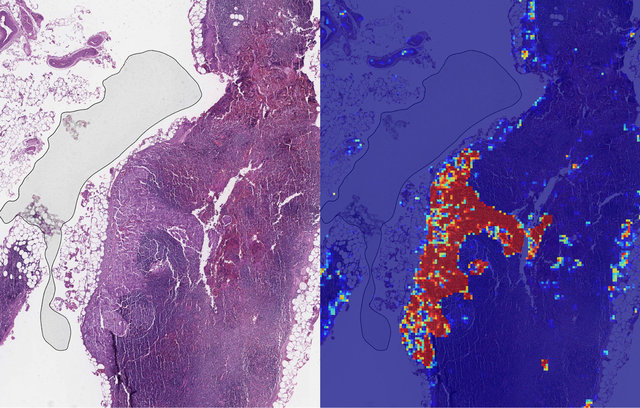

سیستم هوش مصنوعی گوگل سرطان پیشرفته پستان را با دقت 99 درصد و بسیار بهتر از انسان تشخیص می‌دهد.

محققان این غول فناوری، یک ابزار یادگیری عمیق ابداع کرده‌اند که می‌تواند در هنگام مشاهده تصاویر پزشکی، سرطان سینه متاستاتیک(پیشرفته) را با دقت بیشتری نسبت به متخصصان تشخیص دهد.

این تیم الگوریتم خود را آموزش داد تا ویژگی‌های تومور را با استفاده از دو مجموعه تصاویر آسیب شناختی تشخیص دهد و به آن توانایی تشخیص سطح پیشرفته بیماری را در شرایط مختلف داد.

نتیجه یک سیستم هوش مصنوعی بود که می‌تواند تفاوت بین تصاویر بیماران مبتلا به سرطان و غیرسرطانی را با 99 درصد دقت تشخیص دهد.

این سیستم در جستجوی متاستازها و تومورهای بسیار کوچک که حتی انسان معمولا آن را تشخیص نمی‌دهد، بسیار خوب عمل می‌کند.

پاتولوژیست‌هایی که تشخیص بیماری‌ها را بر عهده دارند، دریافتند که این فناوری یادگیری عمیق کارشان را ساده کرده است و نه تنها باعث کاهش میزان عدم تشخیص غده‌های کوچک و متاستازها می‌شود، بلکه زمان بررسی را به نصف رساند و حتی به یک دقیقه هم کاهش داد.